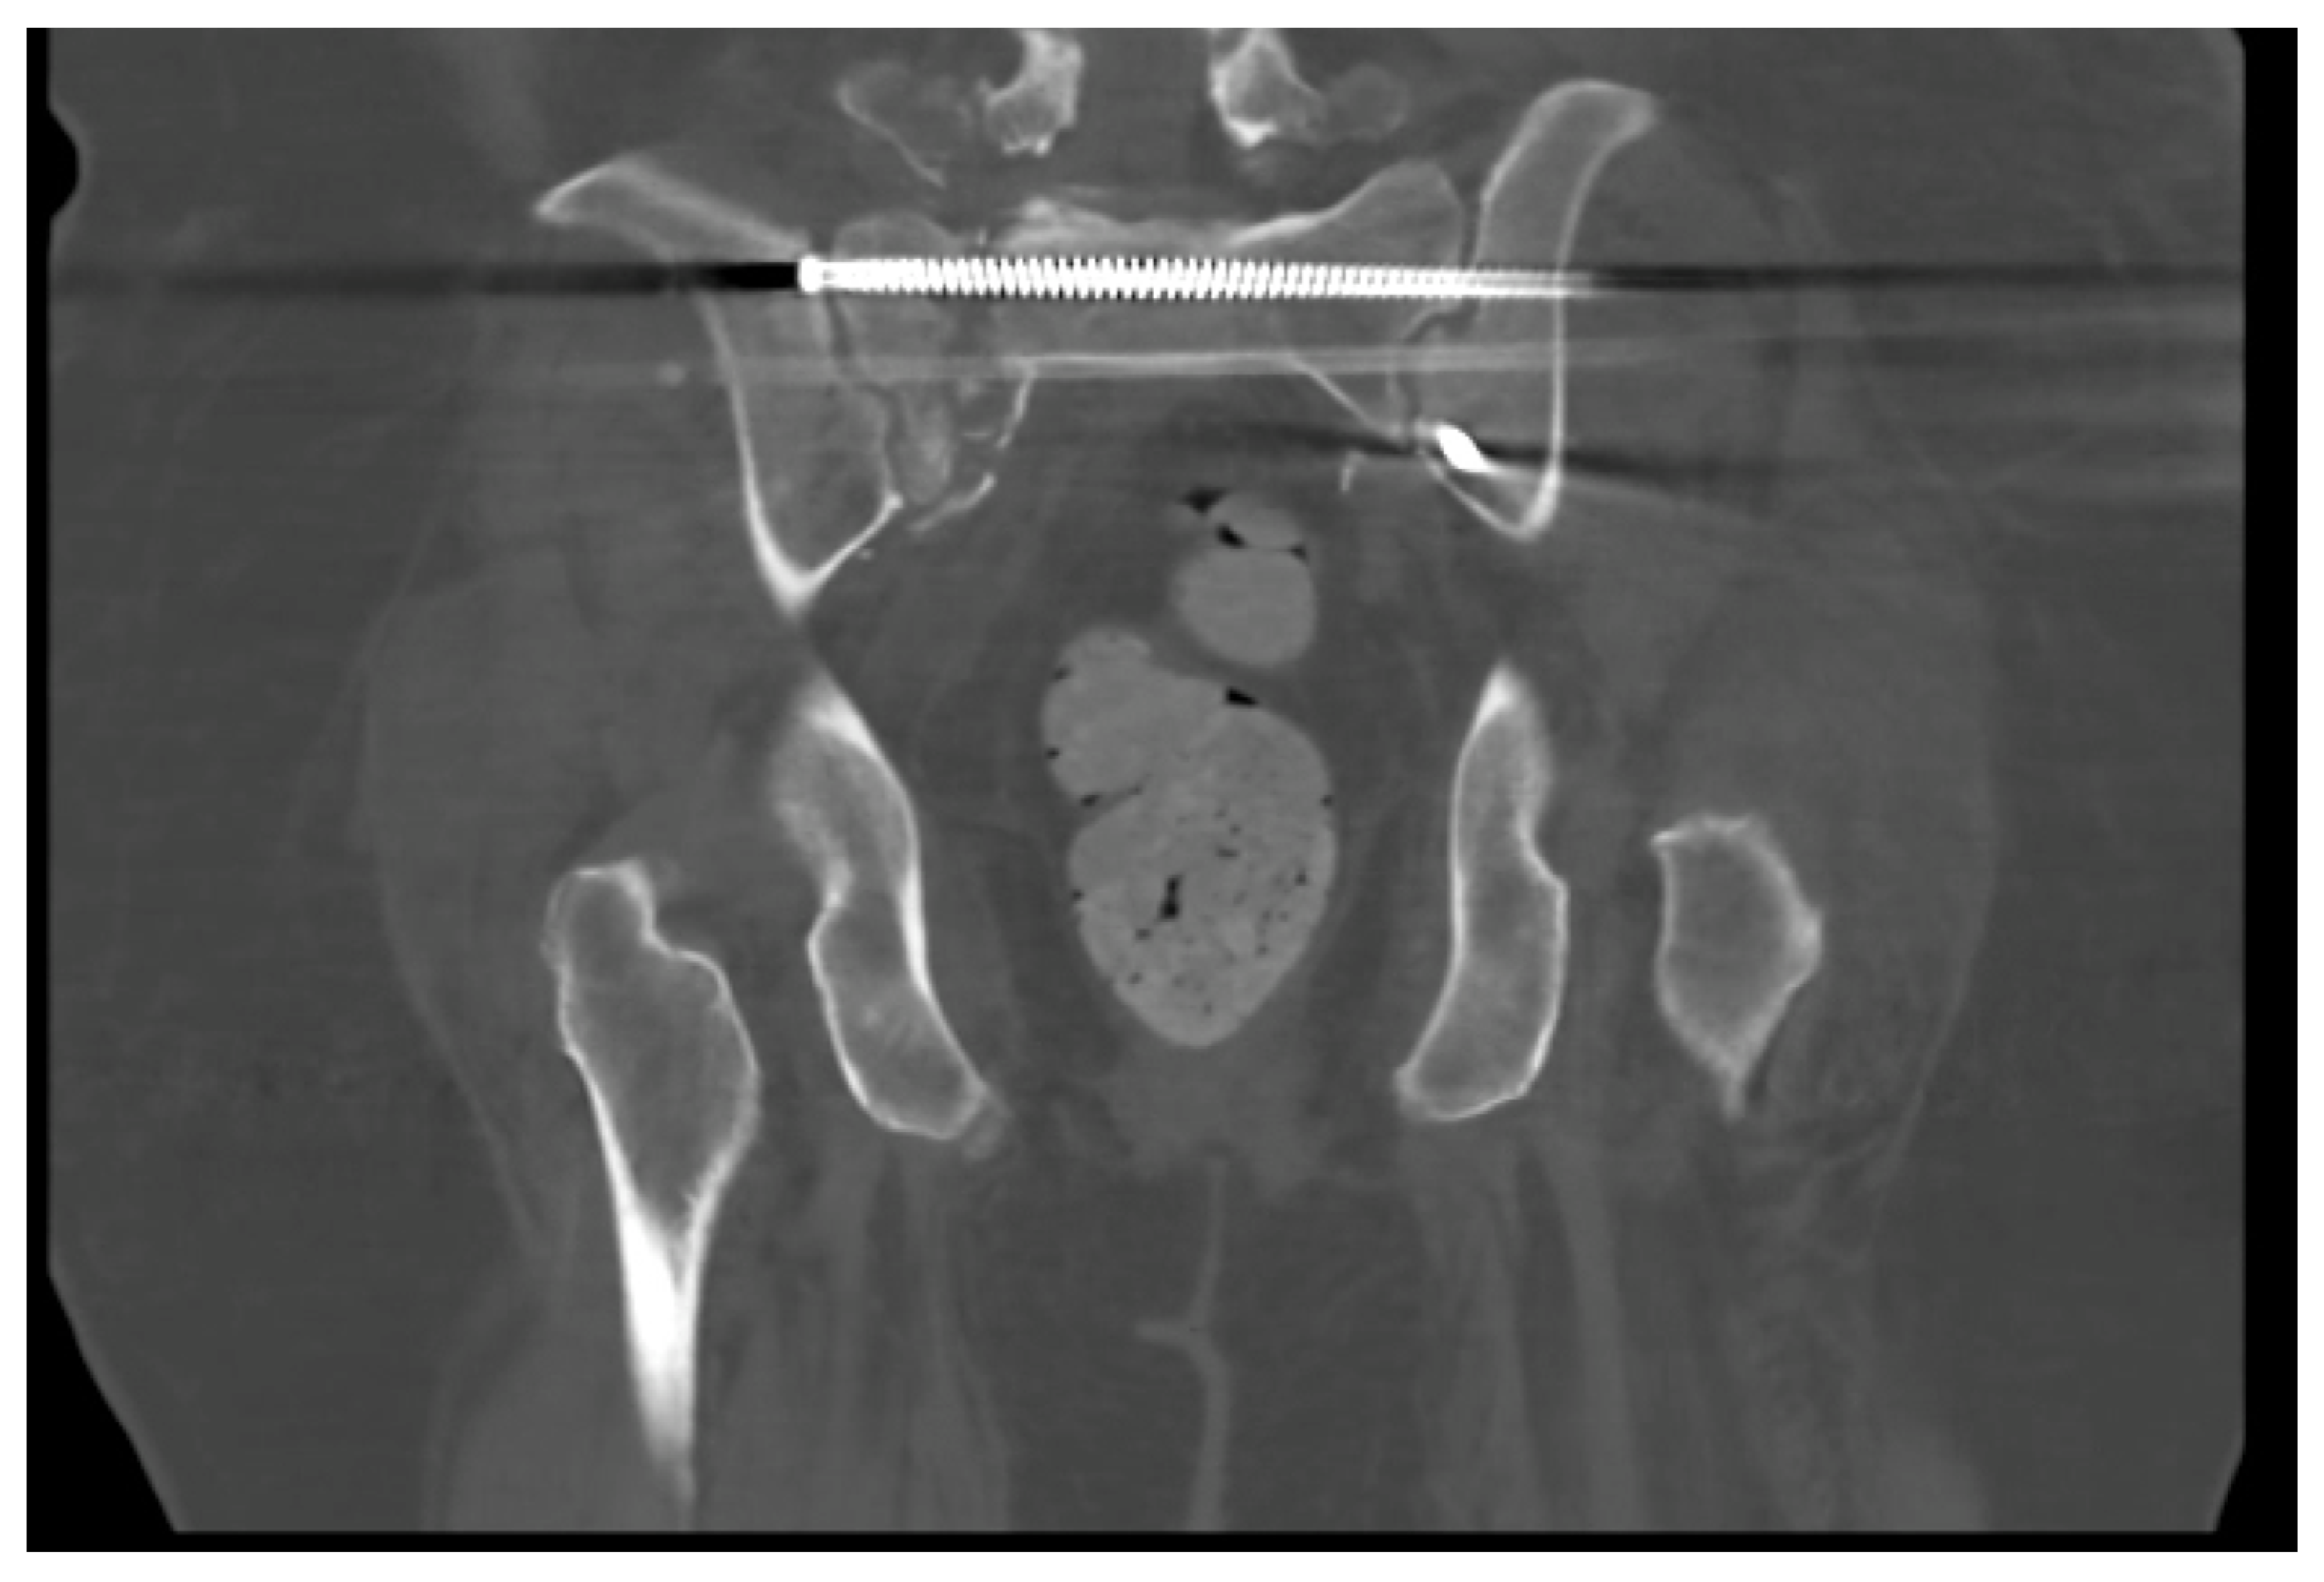

Figure 4.

Still image of coronal CT demonstrating lack of osseous union of vertical shear sacral fracture specifically surrounding trans-iliac trans-sacral screw in S1 corridor.